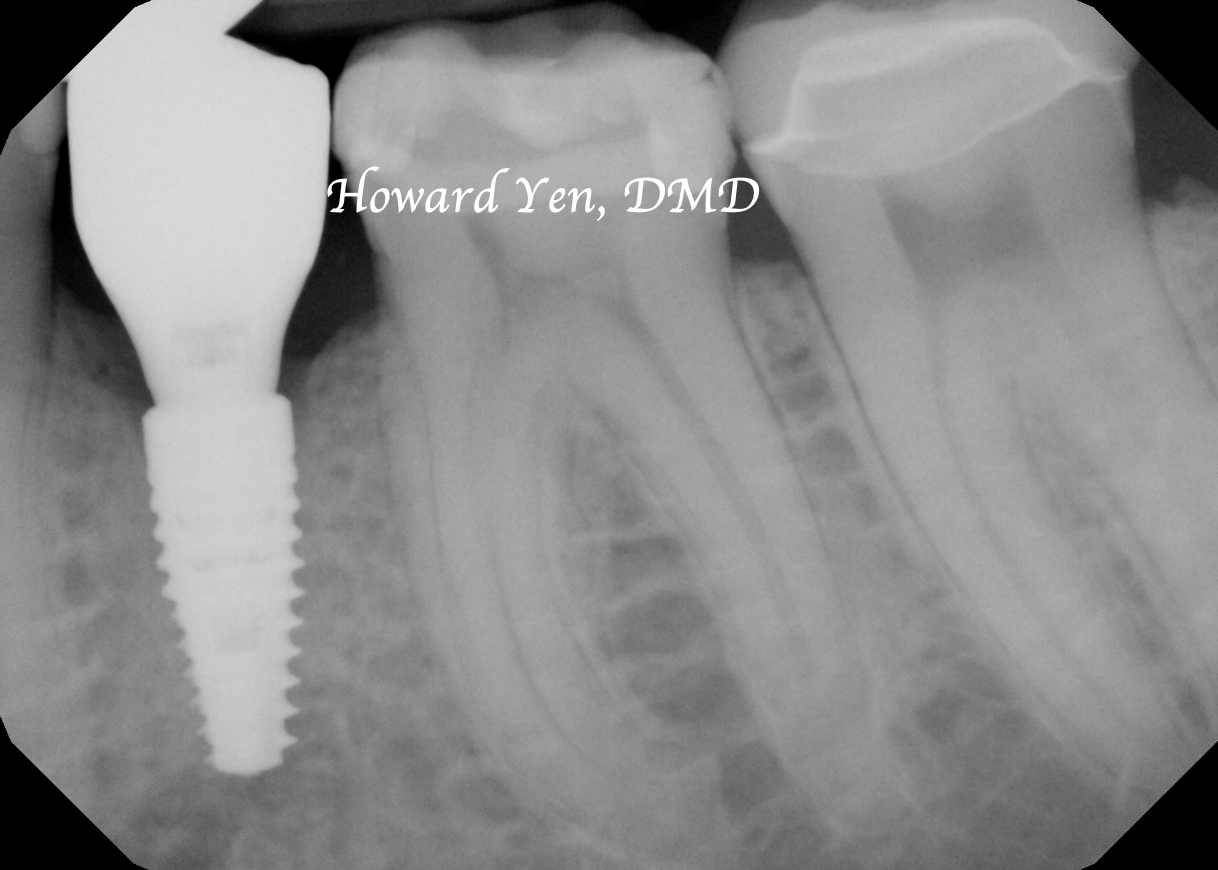

Once a natural tooth is removed from jaw bone, the jaw bone will undergo resorption (shrinkage) in volume. When there is a plan to replace the extracted tooth with dental implant, then there’s some treatment strategies to help reduce the rate of jaw bone shrinkage in order to provide adequate bone volume to receive dental implant. This procedure is often NOT necessary if there’s no plans to replace the tooth nor a strategic value (such as wisdom tooth extractions, the furthest molar in the mouth).